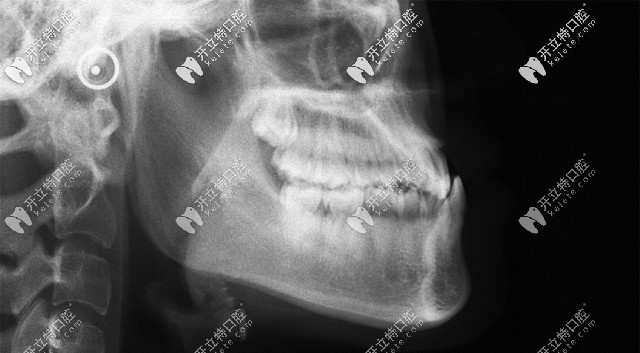

骨性地包天矯正

從這張頭顱側位片,可以清晰的看到顧客牙齒情況是骨性反頜(地包天)▲